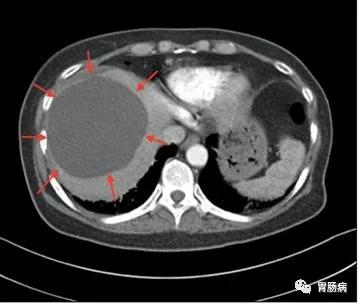

超声是最有效的初检手段,如果需要进一步鉴别,可以再做CT或者核磁共振,甚至穿刺针吸活检等检查。CT如下图所示